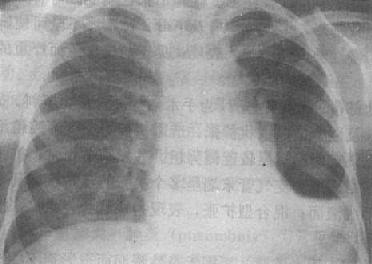

粟粒型肺结核病灶小,透视常难以辩认,故拟诊急性粟型肺结核时应摄片检查。病变早期整个肺野可呈毛玻璃样密度增高。约10日后可出现均匀分布的1.5~2mm大小、密度相同的粟粒状病灶,正常肺纹理常不能显示(图3-1-22)。经过适当治疗后。病灶可在数月内逐渐吸收,偶尔以纤维硬结或钙化而愈合。病变恶化时,可以发生病灶融合,表现为病灶增大,边缘模糊,甚至形成小片状或大片状影,并可干酪样化而形成空洞。

图3-1-22 急性粟粒型肺结核

两肺野布满粟粒状病灶,分布均匀,肺门大

(2)亚急性或慢性血行播散型肺结核:系少量结核杆菌在较长时间内多次进入血流播散至肺部所致。患者抵抗力较强,症灶多以增殖为主,临床症状可不明显或有反复的发热、畏寒或轻度结核中毒症状如低热、盗汗、无力、消瘦等。

由于病灶系多次血行播散所形成,故X线表现为大小不一、密度不同、分布不均的多种性质的症灶(图3-1-23)。小者如粟粒,大者可为较大的结节状,主要分布于两肺上、中野,下野较少。早期播散的症灶可能已经钙化,而近期播散的病灶仍为增殖性或渗出性。本型结核发展较慢,经治疗新鲜病灶可以吸收,陈旧病灶多以纤维钙化而愈合。恶化时病灶可融合并形成空洞或逐渐转为慢性纤维空洞型肺结核。

图3-1-23 慢性血行播散型肺结核

两肺野布满大小不一、密度不同、分布不均的病灶,

下野较少,膈位置低而平